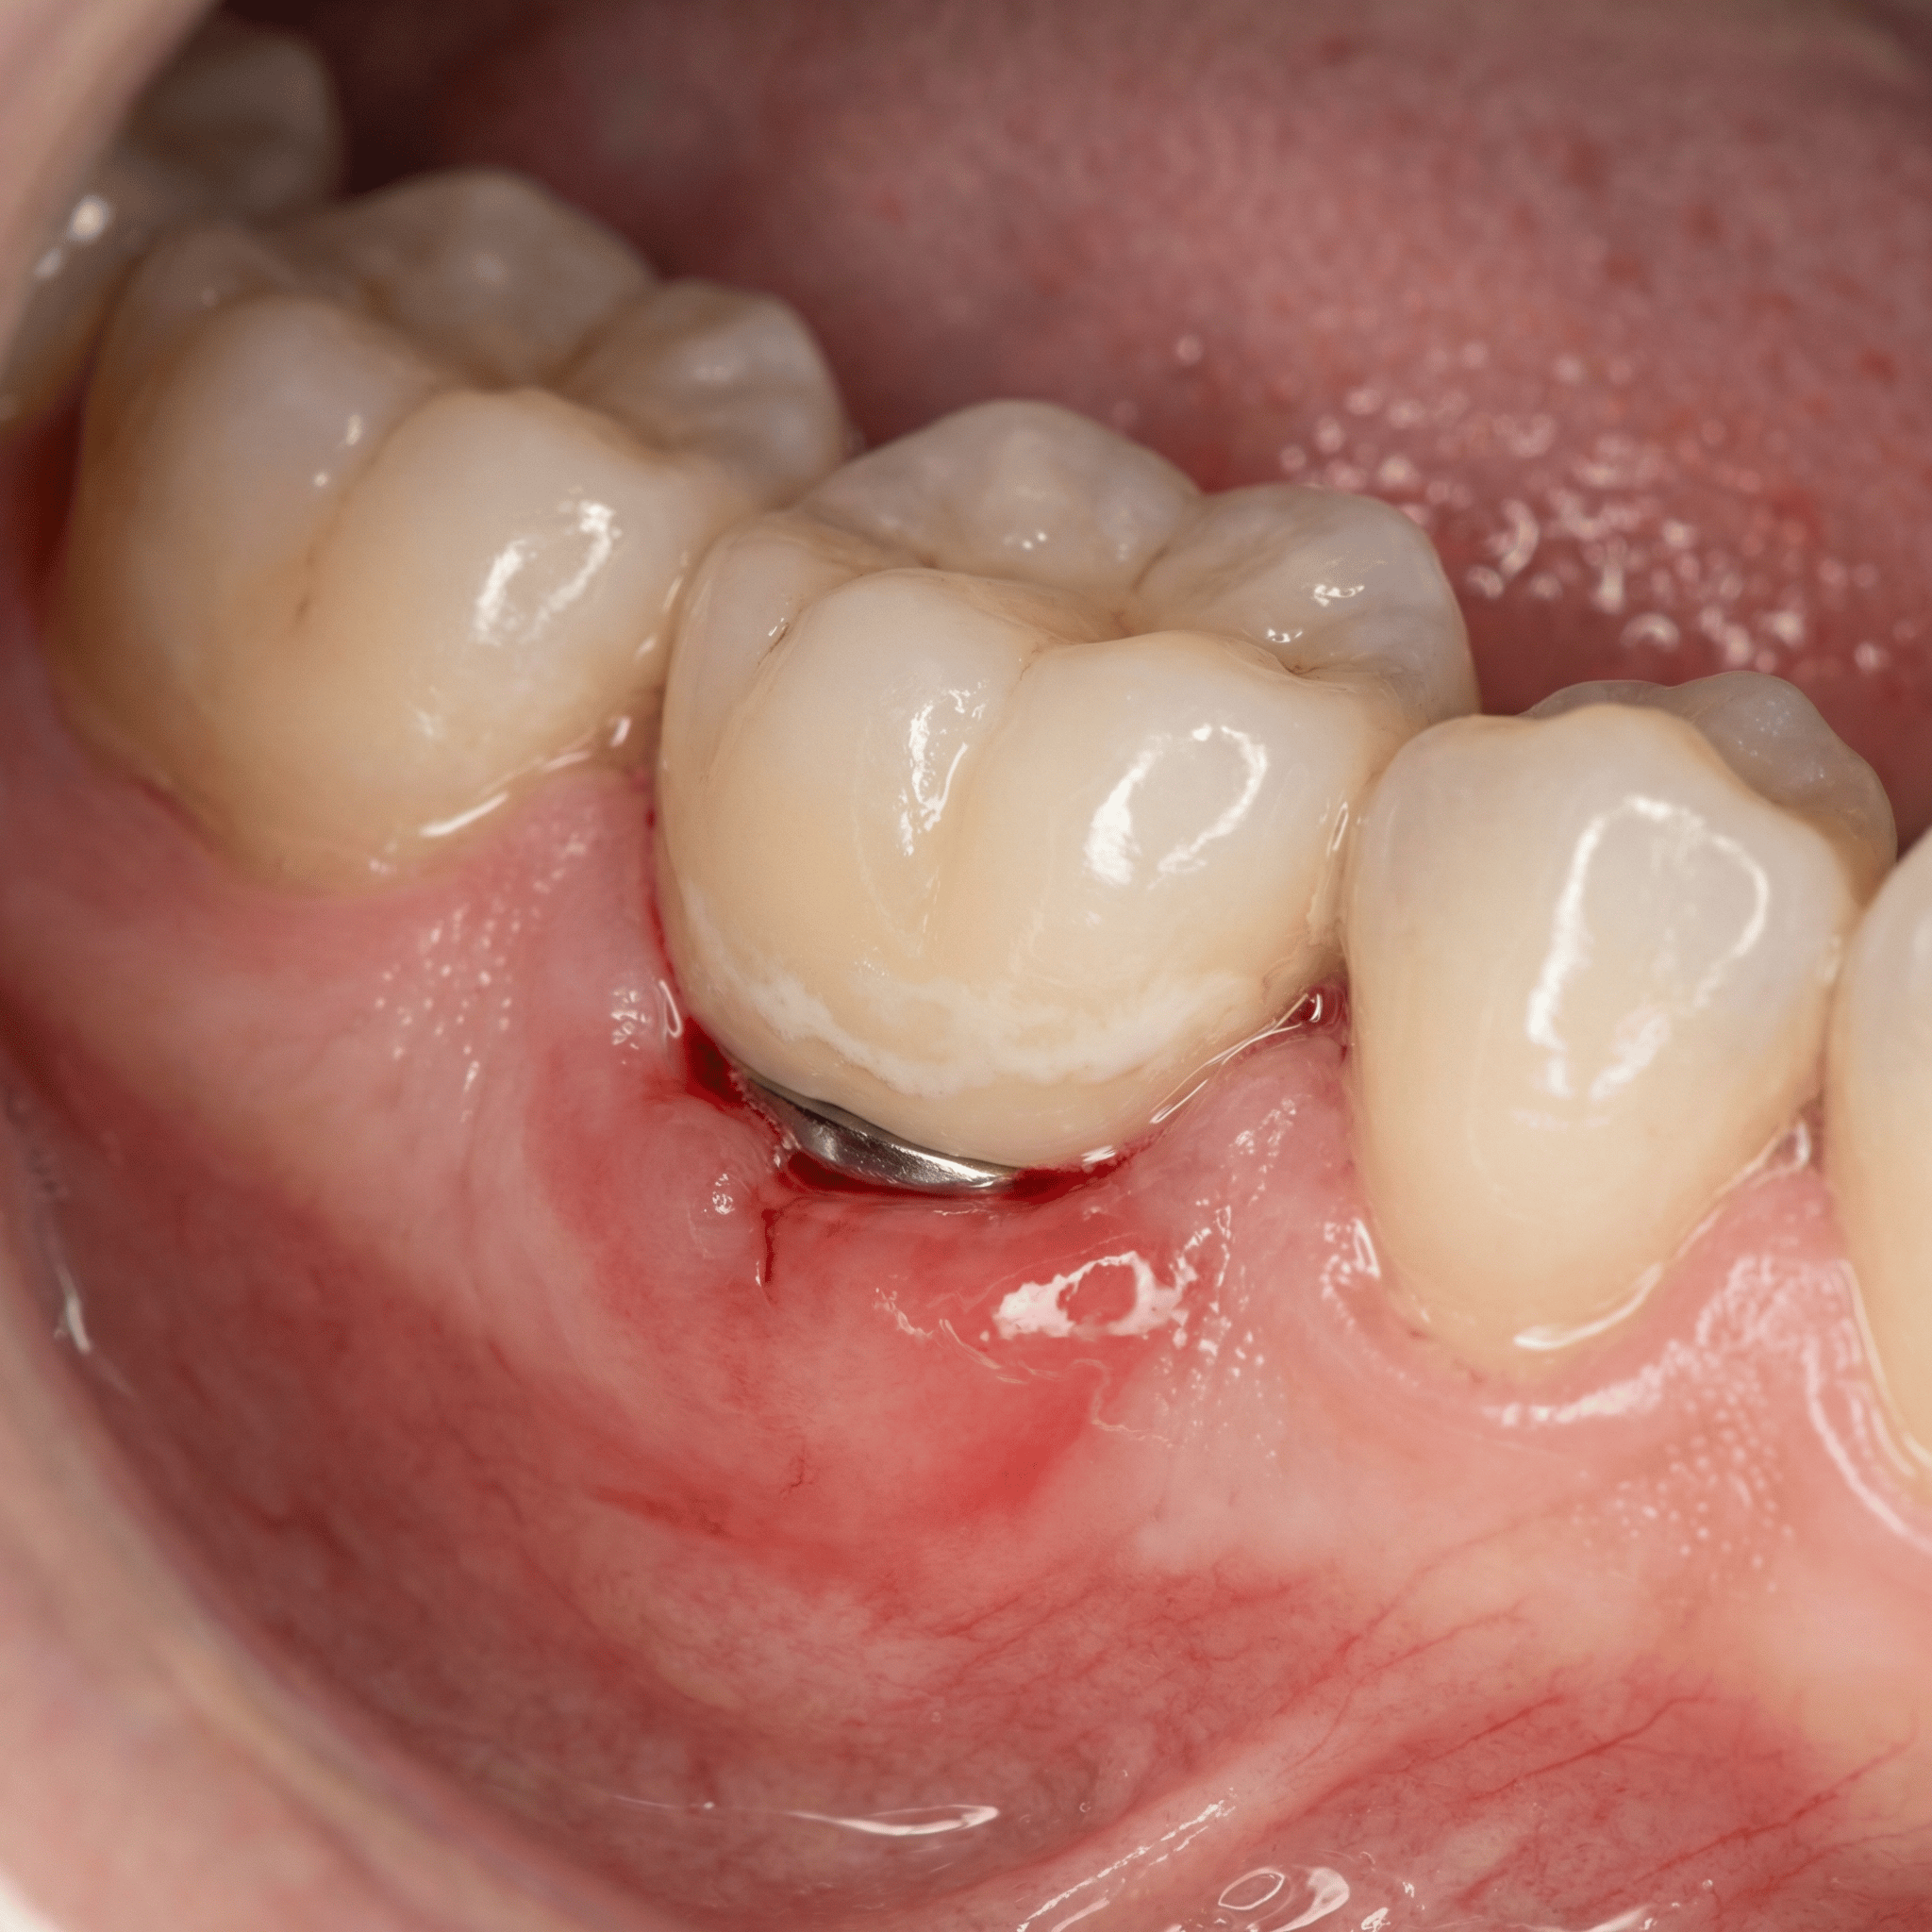

La periimplantitis es una inflamación e infección de los tejidos que rodean un implante dental, acompañada de pérdida de hueso alrededor del implante. Ese detalle del hueso es el que marca la diferencia importante: cuando hay pérdida ósea, la estabilidad a medio-largo plazo se complica.

Antes de llegar a periimplantitis, suele aparecer una etapa previa llamada mucositis periimplantaria. Es similar a una gingivitis alrededor de un diente natural: hay inflamación y puede haber sangrado, pero todavía no hay pérdida de hueso. Esta fase, bien tratada, es reversible. Dicho de otra forma: si pillas la mucositis a tiempo, puedes evitar que se convierta en periimplantitis.

• Encía roja, hinchada o brillante en esa zona.

• Retracción de la encía con exposición de zonas del implante o de la corona.

Exploración clínica y sondaje periimplantario

Se mide la profundidad alrededor del implante con una sonda (de forma cuidadosa). Lo importante no es solo el número, sino si hay sangrado al sondaje, supuración y cambios en el contorno de la encía.